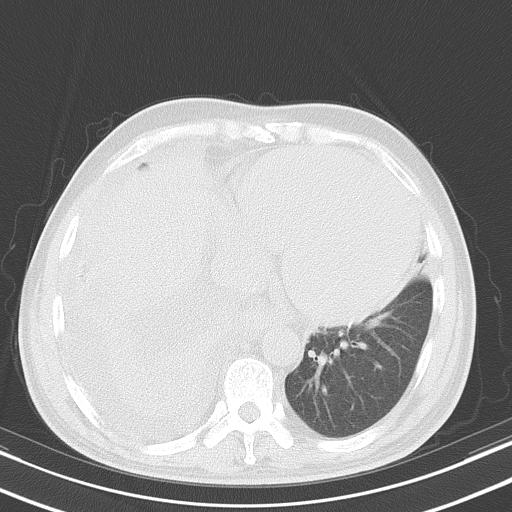

以下是引用zjzjr在2010-3-21 17:39:00的发言:[br]右下中心型肺癌并阻塞性肺炎/不张,纵膈淋巴结肿大,右侧大量胸腔积液,左侧少量胸腔积液

以下是引用zxl51642在2010-3-21 17:06:00的发言:[br]右下中心型肺癌并阻塞性肺炎/不张,纵膈淋巴结肿大,右侧大量胸腔积液,左侧少量胸腔积液,少量腹水。建议纤维支气管镜进一步检查。